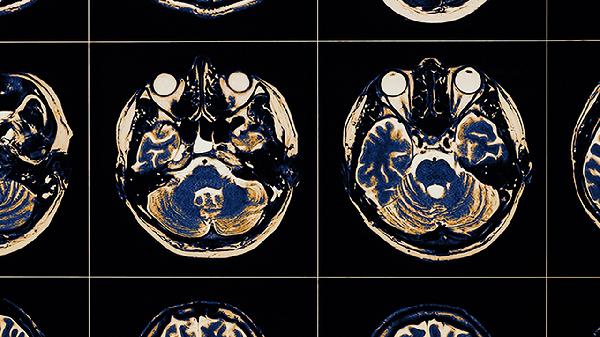

脑血栓片使用期间应注意避免食用辛辣刺激性食物,忌烟酒。服药期间如出现皮肤瘀斑、牙龈出血等异常情况应及时就医。脑血栓患者日常应注意控制血压、血糖、血脂等危险因素,适度运动有助于促进血液循环。饮食上建议低盐低脂,多吃新鲜蔬菜水果。定期复查凝血功能和脑部影像学检查,观察病情变化。